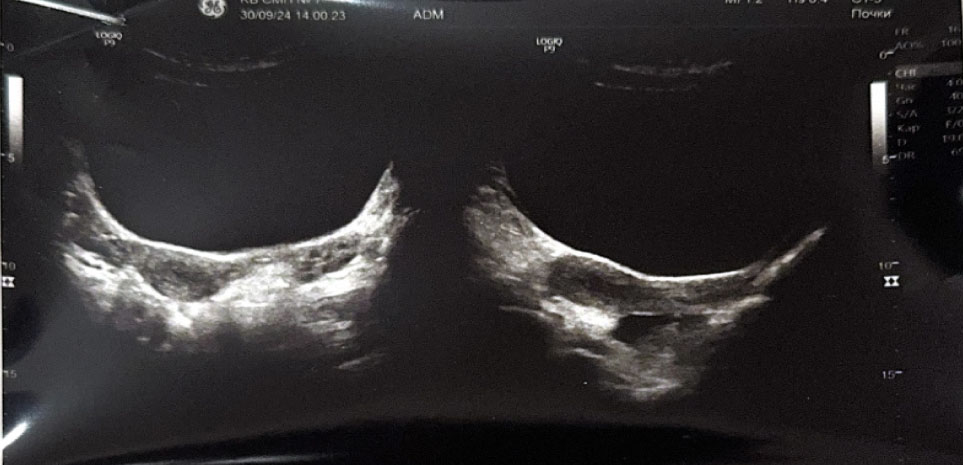

При госпитализации пациентке выполнено УЗИ органов малого таза, выявлено: тело матки смещено вправо, размеры 37 × 26 × 28 мм, миометрий однородной структуры. Толщина эндометрия 3–4 мм, соответствует фазе пролиферации. Правый и левый яичники визуализируются, нормальных размеров без структурных изменений. Слева от матки образование 45 × 42 × 47 мм, средней эхогенности с ровными контурами, соответствует структуре миометрия, толщиной 15–17 мм. В центре образования жидкостной однородный участок, размерами 29 × 30 мм (гематометра?). Выше и каудальнее левого яичника лоцируется тубулярное анэхогенное образование толщиной 4–6 мм протяженностью 30 мм (маточная труба?). Заключение: аномалия развития матки (матка с рудиментарным рогом слева). Гидросальпинкс слева. Гематометра слева (рис. 1, 2).

Рис. 1. Ультразвуковое исследование органов малого таза. Аномалия развития матки

Рис. 2. Ультразвуковое исследование органов малого таза. Рудиментарный замкнутый рог матки